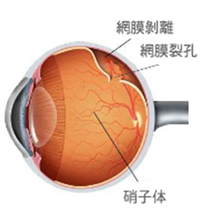

飛蚊症

視界にごみや虫のようなものが飛んでいるように見える症状を飛蚊症と呼びます。特に治療が必要でない「生理的」なものと、治療をしないと視力が低下する恐れのある「病的」なものに分けられます。

| 考えられる原因 |

生理的飛蚊症 硝子体(しょうしたい)が年齢により濁るためにおこります。 病的飛蚊症 網膜剥離、網膜裂孔、硝子体出血、ぶどう膜炎などの疾患により付随して起こる飛蚊症です。手術や処置などの早期治療を行わないと失明する恐れもあります。 |

|---|---|

| 検査 |

|

| 主な治療法 |

生理的な飛蚊症の場合は、特に治療はありません。 |

網膜剥離・網膜裂孔

網膜剥離とは、眼球の内側にある網膜という膜が剥がれて、はがれた部分の視野が欠けたり、網膜の中心部である黄斑部分まで剥がれた場合は、急激に視力が低下し、失明に至る恐れもあります。

| 主な症状 |

|

|---|---|

| 考えられる原因 |

|

| 検査 |

|

| 主な治療法 |

レーザー治療(網膜光凝固術) 網膜裂孔や最小限の網膜剥離では同日速やかにレーザー治療を行います。 硝子体手術 進展した網膜剥離では入院、手術が必要になります。連携病院に紹介しています。 |